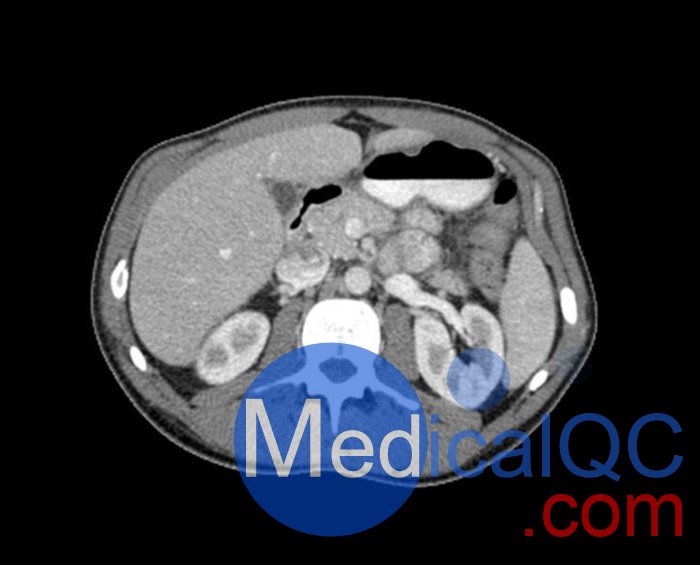

WEK57-01門靜脈期軀干模體,WEK57-01軀干模型模擬了門靜脈期的造影劑增強胸部、腹部和骨盆。它覆蓋了會陰的第二胸椎。

該模型可用于 CT(包括 CBCT)以評估和優化成像性能和后處理應用,包括支持 AI 的應用。它也適用于培訓目的。

該模型提供了對軟組織和骨組織的詳細而逼真的模擬。包括肺在內的空隙充滿了大約 -160HU的纖維素聚合物復合材料。

真實模擬脈管系統、骨骼和軟組織,包括肺、心臟、肝臟、膽囊、胰腺、脾臟、腎上腺、腎臟、胃、小腸、結腸、膀胱和前列腺。

WEK57-01門靜脈期軀干模體,WEK57-01軀干模型成像效果圖: